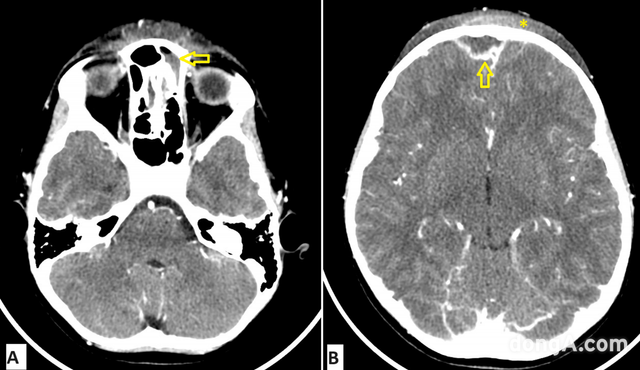

사진=Cureus 5월 호 캡처.

CT 검사 결과, 급성 전두동염(이마 부위 축농증)이 두개골과 그 주변으로 퍼졌다는 사실이 밝혀졌다.

의료진은 뇌와 가까운 부위까지 감염이 퍼지는 희귀 질환인 ‘팟츠 퍼피 종양(Pott’s Puffy Tumor)’을 진단했다.

아이에게는 이마 뼈 속에 고름이 고인 ‘골수염’과 ‘피하 고름집’, ‘두피 염증’까지 나타났다.